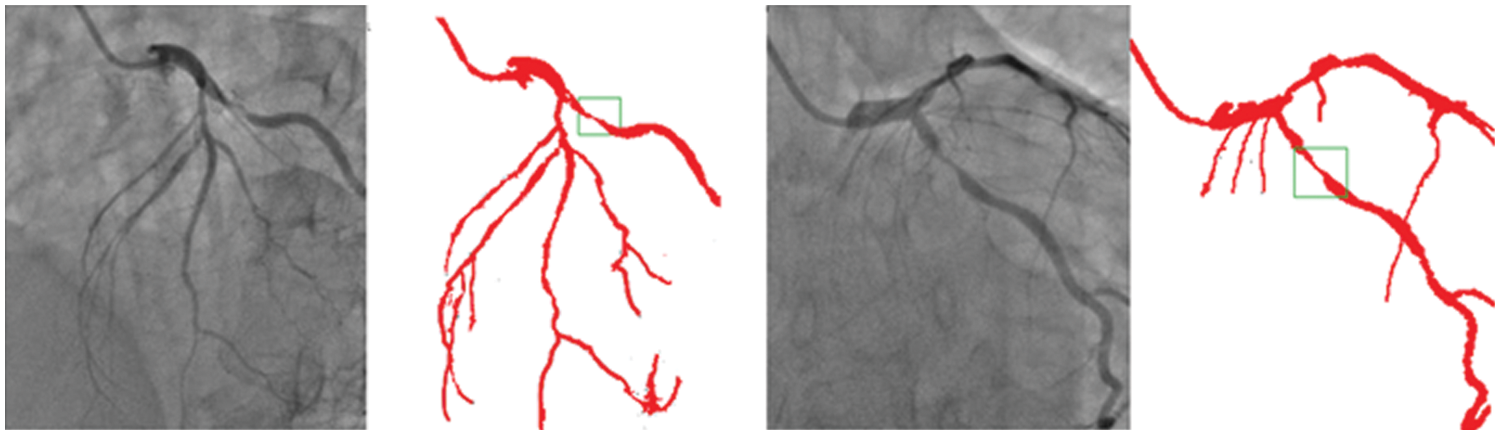

Though there is some declining trend of coronary artery disease in the developed nations due to proper implication of lifestyle, measures, the extent of the disease is ever increasing in other parts of the world. In India, the situation is particularly gloomy because this disease can be seen in much younger age due to genetic problems. The incidence of CAD in young Indians is 12%–16%, which is higher than any other ethnic group in the world [30–34]. It is really surprising that 25% of heart attacks in India affect individuals less than 40 years of age. So, it is important that newer and novel technologies combating the situation must be developed. Our current effort is to segregate and improve the coronary angiogram images using the CNN model. We have highlighted that the proposed technique helps better understand coronary anatomy and luminal stenosis. A similar exercise with a larger sample size will further enhance this insight. The identified segmented regions of the images for the corresponding input coronary angiograms are given in Fig. 7. The identified region is the thin region in the vessel that is affected by the coronary artery disease resulting in the accumulation of fats making the blood flow pass from a lesser available area. In our study, the proposed models have shown high-performance detection in coronary vessels. Therefore, it has the potential to assist heart surgeons to understand the profiling of coronary arteries blockage, especially from the 2D images.

Figure 7: Identified regions from the segmented images for the corresponding input angiograms